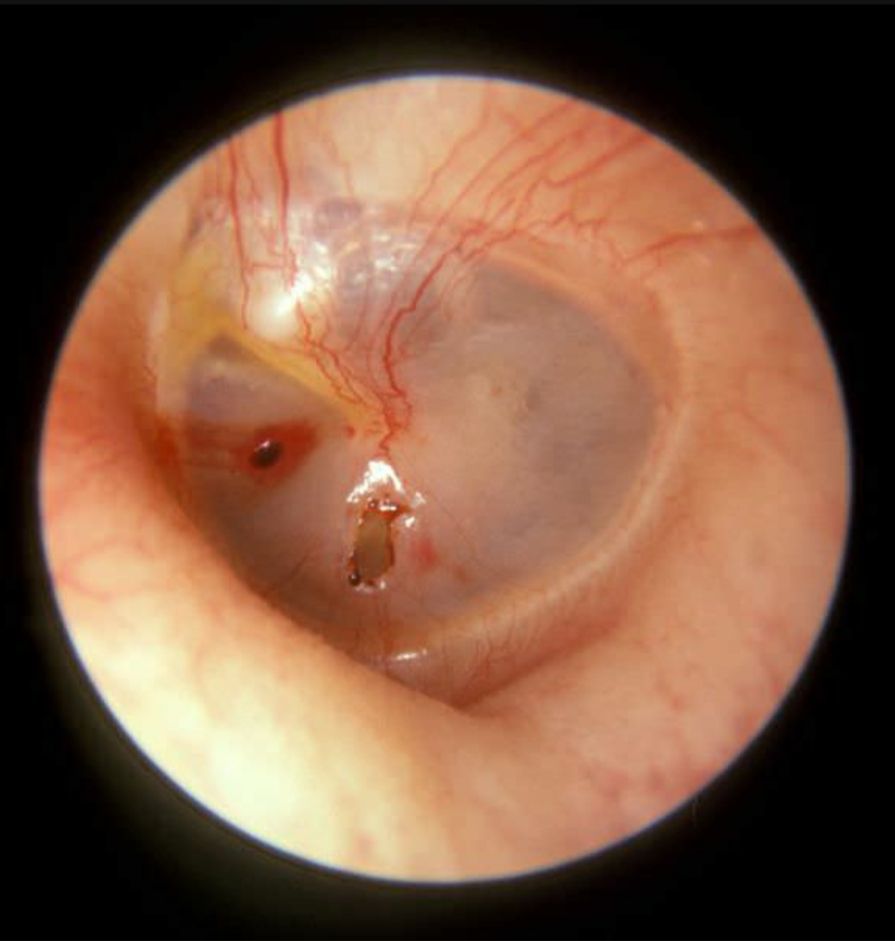

Left tympanic membrane traumatic perforation